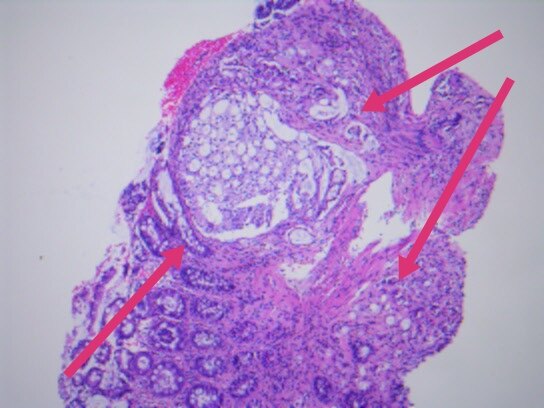

几天前,入我院行肠镜检查,并活检,显微镜下可见癌浸润于直肠粘膜之间。

最终,我们以上述HE形态为线索,老年男性,直肠占位,为XY坐标,我们初步音箱诊断就是前列腺腺泡腺癌浸润至前列腺腺外,累及直肠并形成肿块,浸润直肠全层至粘膜内。